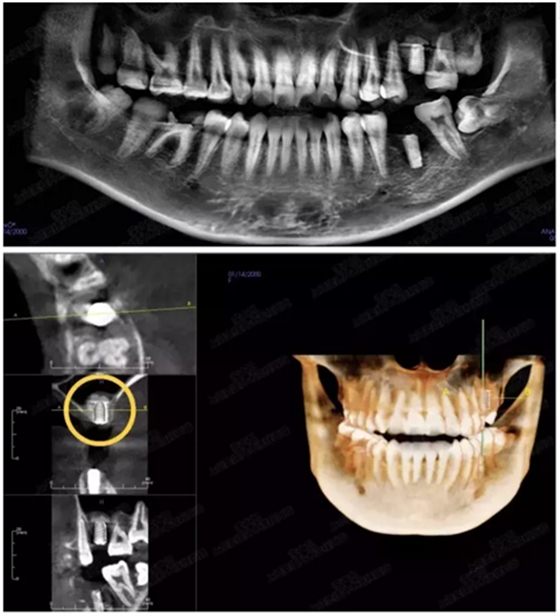

病例五

剩余不足1mm

112.png

提升10mm

113.png